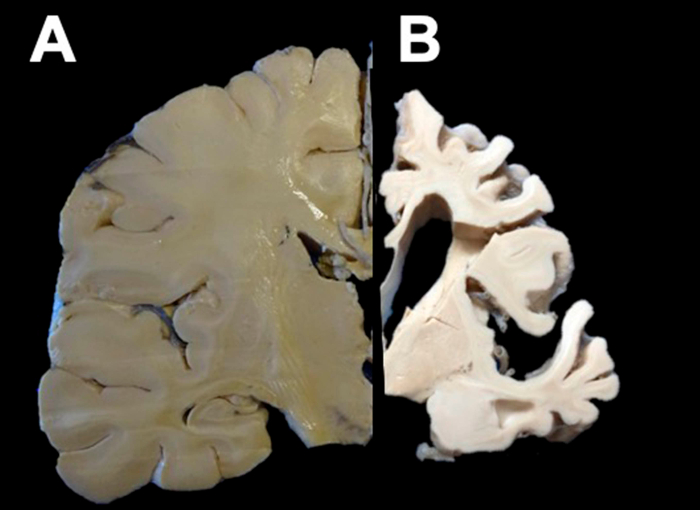

José Luna Muñoz, director del BND, explicó que un análisis específico requiere de la examinación de áreas del cerebro como encéfalos y fragmentos de órganos de los fallecidos que tenían alguna enfermedad neurodegenerativa y de personas sin afecciones neurológicas para realizar una comparación del procesamiento molecular patológico.